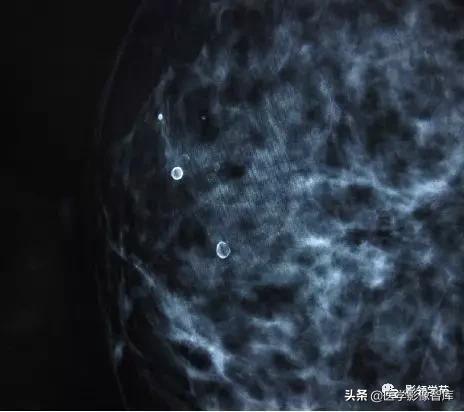

6. Round and punctate calcifications

- 圆形钙化的大小在0.5-1mm,常见于终末导管小叶单元的腺泡。<0.5 mm,称为点状钙化。

- BI-RADS2:散在的环形钙化。

- BI-RADS3或4级:孤立的簇状钙化或新出现的或位于肿瘤同侧的钙化。